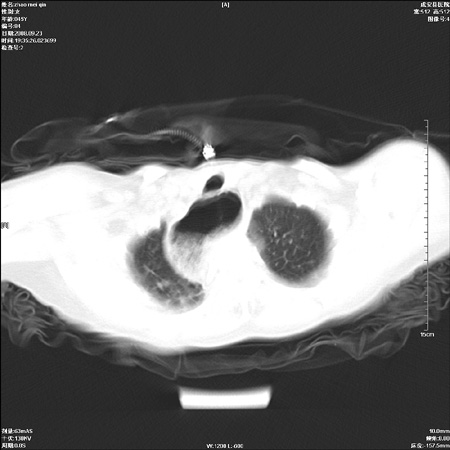

标题: CT15861:女 60 外伤后1小时 胸疼 [打印本页]

标题: CT15861:女 60 外伤后1小时 胸疼

外伤后1小时 胸疼 是外伤后引起的吗?

食道扩张明显下端逐渐变窄,倒像贲门失迟缓

食道ca术后胸腔胃,右肺挫伤?

非外伤性改变,典型的贲门失迟缓症

食道扩张明显下端逐渐变窄,大量食物存留,象贲门失迟缓症。